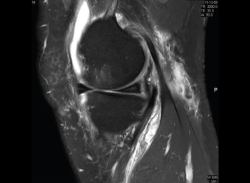

1.2. Ligamentos

Se visualizan como estructuras lineales hipointensas en todas las secuencias.

1.2.2. Ligamento cruzado anterior (LCA) (Figuras 40, 41, 42, 43 y 44)